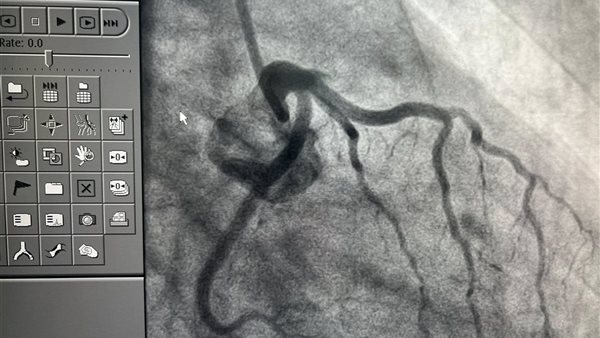

وقال في منشور له عبر حسابه على موقع التواصل الاجتماعي فيس بوك مرفقا بعدد من الصور للفحوصات الخطيرة للشباب: خلال ثلاثة أيام فقط من عيد الأضحى، استقبلنا بالمستشفى 13 حالة طوارئ مصابة بجلطات حادة في القلب، وجميعها من فئة الشباب الذين لا يعانون من أي أمراض مزمنة أو عوامل خطر تقليدية كارتفاع ضغط الدم أو مرض السكري، والعامل المشترك الوحيد بينهم كان تعاطي الحشيش.

وتابع حلمي راصدًا حجم المعاناة: كما استقبلنا شابًا يبلغ من العمر 28 عامًا، لا يعاني من أي أمراض مزمنة، لكنه أصيب بجلطة حادة بالقلب وكان الشريان التاجي في حالة سيئة جدًا لا تتناسب مع سنه، وفي حالة أخرى، شاب في الثانية والثلاثين من عمره خرج من مستشفى بعد فحص أولي طبيعي، لكن مع أول رسم قلب عندنا ظهر ارتفاع ST واضح، وتبين في القسطرة أن الشريان التاجي الأمامي النازل كان غير ظاهر تمامًا، وكدنا نظن أنه غير موجود، لكننا بفضل الله وبتعاون فريق القلب في المستشفى استطعنا تحديده وتوسيعه وتركيب دعامة لإنقاذ حياته.